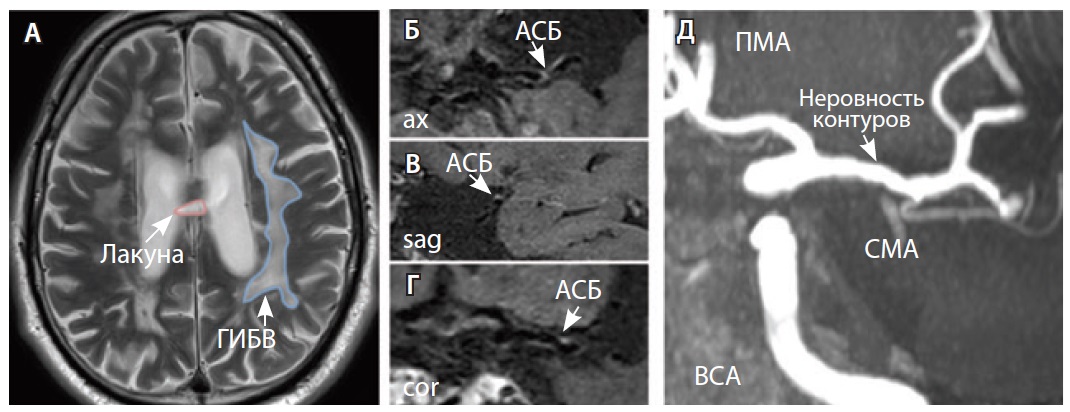

У всех включенных в исследование пациентов определялись атеросклеротические изменения брахиоцефальных артерий, в том числе на интракраниальном уровне, разной степени выраженности. У 9 больных отмечались признаки отрицательного ремоделирования артерий – выявление АСБ в стенке артерий, без сужения их просвета. Присутствовали изменения вещества головного мозга: инфаркты, в том числе лакунарные, – в 17 (58%) наблюдениях; МРТ-признаки церебральной микроангиопатии (ЦМА) – у 20 (68%) пациентов, среди них со степенью выраженности (F) по шкале Fazekas: F1 – у 7 (35%), F2 – у 4 (20%) (рис. 3), F3 – у 9 (45%) (рис. 4) [27]. Средние, большие и обширные инфаркты мозга зарегистрированы у 6 (20%) больных. Для количественной оценки изменений АСБ выбирался наиболее пораженный участок артерий (за исключением окклюзии): в 12 (41,4%) случаях это был интракраниальный сегмент внутренней сонной артерии (ВСА), в 10 (34,5%) – средней мозговой артерии (СМА), в 6 (20,7%) – базилярной артерии (БА), в 1 (3,4%) – задней мозговой артерии (ЗМА) (см. табл. 1).

Рис. 3. Пациент Ц., 53 года, с признаками церебральной микроангиопатии (F3 по шкале Fazekas), атеросклерозом интракраниальных артерий, без формирования гемодинамически значимых стенозов. А – магнитно-резонансная томография (МРТ) головного мозга, режим Т2-взвешенного изображения: видны обширные сливные зоны гиперинтенсивности белого вещества (ГИБВ) с наличием на этом фоне лакунарных инфарктов; Б, В, Г – МРТ сосудистой стенки, режим T1-TSE-db-FS после контрастного усиления: в сегменте М1 левой средней мозговой артерии (СМА) визуализируется эксцентричная атеросклеротическая бляшка (АСБ), интенсивно накапливающая контрастный препарат; Д – трехмерная магнитно-резонансная времяпролетная (3D ToF) ангиография: выявляется неровность контуров левой СМА в сегменте М1; ax – аксиальная, sag – сагиттальная, cor – коронарная плоскости; ВСА – внутренняя сонная артерия; ПМА – передняя мозговая артерия